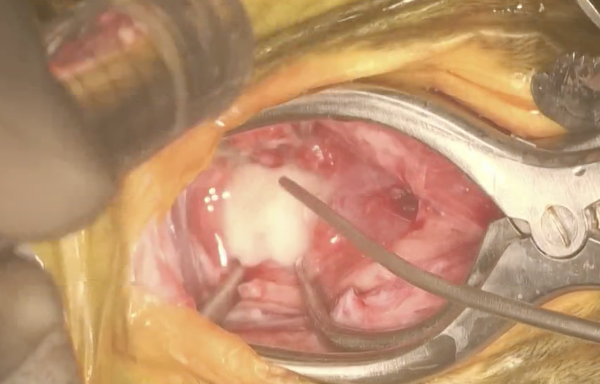

手術では、環椎と軸椎を露出するために腹側アプローチ(ベントラルアプローチ)を行い、骨の癒合を促進して安定化させるために関節軟骨を切除します。次に環軸椎を貫通するようにピン(スレッドピン)を入れ関節固定を行います。Cアームを用いながら行うことで安全性が向上します。左右二本ずつ入れたら、環椎にも2本、軸椎にも2本挿入します。位置が大丈夫かどうかをCアームで確認し、先程削った軟骨の部分に上腕骨から採取した海綿骨を移植し、最後に骨セメントを入れて固定して終了となります。

左が頭で右が尾であり、左側の骨が環椎、右の骨が軸椎です。

骨セメントを入れたところです。空気と触れると硬化してセメントのようになります。

それらのピンを切ってから海綿骨を移植して骨セメントを入れたところになります。熱が発生するため積極的に冷やしています。